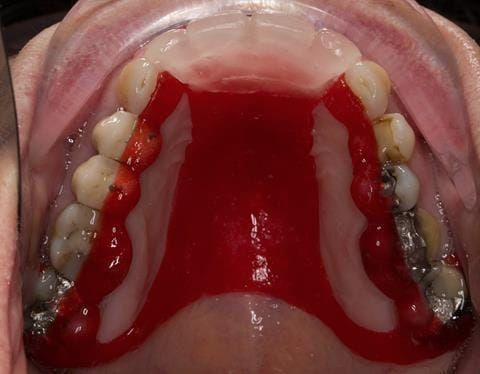

- High smile line showing gum above gingival zeniths of upper front teeth when smiling. Aesthetic failure of the upper four incisors with inflammation of the gingivae and mis-match of the gingival zenith levels.

- Other than the maxillary incisors the remaining dentition was in marginally better condition being moderately to heavily restored. Many will probably require replacement and restoration from time to time mainly from wear and tear owing to occlusal forces.